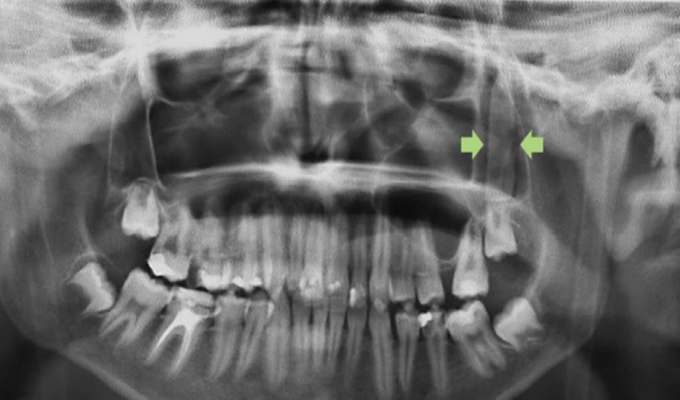

Una radiografía reveló la existencia de un objeto rectangular de unos 3,5 centímetros de longitud en uno de sus pómulos.

En el centro médico le realizaron una radiografía y tomografía computarizada que reveló la existencia detrás de un pómulo de un objeto rectangular de unos 3,5 centímetros de longitud "que tenía forma de hoja de cuchillo".